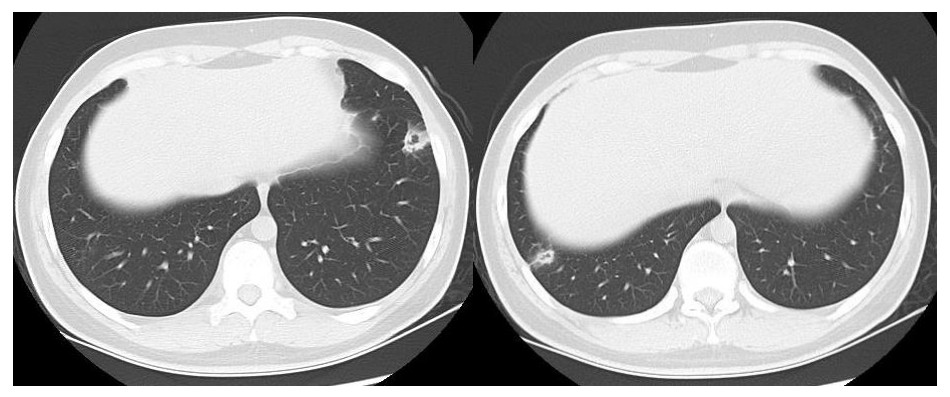

患者男性,21岁,主因“间断发热、寒战伴头晕头痛2周”于2021年11月18日急诊收入院。患者诉2周前进食烧烤后出现发热,体温最高可达42℃, 伴畏寒、寒战、咽痛、头晕、头痛、乏力,就诊于本院耳鼻喉科后,查体见扁桃体有脓点,快测降钙素原(procalcitonin,PCT)为37.27 ng/mL,胸部CT检查未见异常,考虑诊断为“急性化脓性扁桃体炎”,先后给予左氧氟沙星、阿奇霉素抗感染及甲泼尼龙控制炎症后上述症状未见明显好转,为进一步治疗,收入急诊病房治疗,既往体健,入院时查体:体温41℃,脉搏98次/min,呼吸频率23次/min,血压120/60 mmHg(1 mmHg=0.133 kPa),患者神志清楚,急性病容,精神较差,颈部浅表淋巴结触及肿大,右侧较大约2.0 cm ×0.5 cm,左侧较大约1.3 cm×0.7 cm,质软,活动度好,界限清楚,有压痛,表面皮肤无红肿,无破溃,双肺呼吸音清,未闻及干湿性啰音,心脏听诊无杂音,腹软,无压痛及反跳痛,双下肢无水肿。血常规检查白细胞计数10.49×109/L, 中性粒细胞百分比94.6%,血红蛋白120 g/L, 血小板计数107×109/L,PCT 42.83 ng/mL,白介素6(interleukin, IL-6)980.30 pg/mL,C反应蛋白211 mg/L,G试验、GM试验阴性。胸部CT检查示右肺上叶可见一单发实变影,其内可见空洞(图 1)。根据病史、查体和辅助检查考虑诊断为肺脓肿,给予注射用哌拉西林钠他唑巴坦4.5 g Q8h治疗,入院第2天,患者仍有发热,体温最高38.7℃,给予对症处理,入院第3天患者体温峰值有所下降,体温维持在37~38℃,考虑抗炎有效,痰培养结果回报为纹带棒杆菌,草绿色链球菌(奈瑟菌属),考虑这2种细菌为皮肤或口腔的正常菌群,为条件致病菌,该细菌导致发热的可能性较小,继续给予哌拉西林钠他唑巴坦治疗。入院第5天血培养回报血液中找到坏死梭杆菌,考虑为血流感染。加用甲硝唑1 g每8 h一次抗感染治疗,复查血常规白细胞计数8.14×109/L, 中性粒细胞百分比81.5%,血红蛋白120 g/L, 血小板计数246×109/L,PCT 3.43 ng/mL,IL-6 13.04 pg/mL,C反应蛋白5 mg/L,炎性指标较前明显下降,考虑抗炎治疗有效,继续目前抗生素治疗。入院第10天患者体温仍有低热,体温36.5~37.5 ℃,复查胸部CT见双肺多发小结节,双肺多发空洞病变,考虑炎性可能(图 2)。颈静脉超声检查提示患者左侧颈内静脉血栓形成,给予依诺肝素0.4 mL每12 h一次抗凝治疗,根据血培养结果、胸部CT表现和颈静脉超声结果,考虑该患者诊断为坏死梭杆菌导致Lemierre综合征(Lemierre syndrome, LS)。用哌拉西林钠他唑巴坦联合甲硝唑治疗后仍有低热,化验检查PCT为0.30 ng/mL,IL-6为3.52 pg/mL,C反应蛋白为3 mg/L,胸部CT示肺部空洞较前增加,考虑感染未完全控制,改为调整抗生素为比阿培南0.6 g每12 h一次联合甲硝唑1g每8 h一次抗感染治疗,治疗1周后患者体温恢复正常,CT检查示双肺多发空洞消失,残留少量索条影(图 3),患者病情好转出院,出院带药给予口服甲硝唑联合阿莫西林抗感染治疗,利伐沙班抗凝治疗,随诊2周后复查胸部CT正常。

空洞病变消失,残留少量实变及索条影 图 3 入院第19天胸部CT

LS的致病菌主要为坏死梭杆菌,因此LS也被称为坏死梭杆菌病,其他致病菌包括核杆菌、类杆菌、链球菌和葡萄球菌等[5]。坏死梭杆菌为厌氧革兰阴性多形态杆菌,广泛存在于人类和动物的口腔、上呼吸道、胃肠道和泌尿生殖道的正常菌群。坏死梭杆菌可以产生白细胞毒素、内毒素、溶血素和血细胞凝集素等,白细胞毒素和溶血素与脓肿形成相关,血细胞血凝素可引起动静脉血栓形成,可导致转移性脓肿,弥漫性血管内凝血和血小板减少也与此有关[6]。患者起初为咽部感染,然后通过咽旁间隙侵袭至颈内静脉,形成颈内静脉血栓,脓毒性栓子随着血流播散至肺部,引起肺部脓肿和肺栓塞。本例患者刚发热时胸部CT正常,门诊给予喹诺酮类药物和大环内酯类药物治疗2周后,入院时胸部CT示患者右肺中叶单发实变影,其内可见空洞样变,后随病情发展,胸部CT示双肺多发肺空洞样变,符合LS的临床表现。LS最初表现为喉咙痛或颈部疼痛, 但可出现多种非特异性症状, 如全身僵硬、寒战、发热、颈部淋巴结肿大、眼眶疼痛、骨/关节疼痛、四肢无力、恶心、呕吐等胃肠道症状。最初感染1周后,可以在血液中找到细菌,然后在颈静脉内脓毒性血栓形成,可以肺内形成肺脓肿和脓胸,也可以累及关节[7]